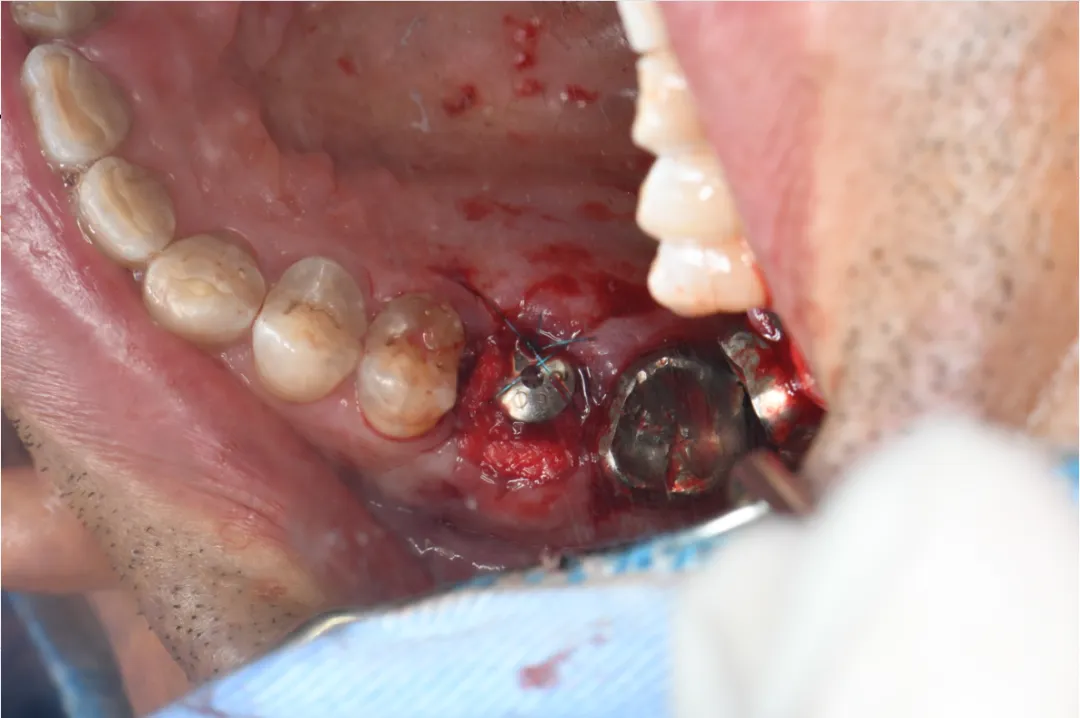

病例分享:患者男,诊断左上六慢性根尖炎劈裂;处置:基础治疗+即刻种植(种植前中后进行光动力疗法照射1min(2次)